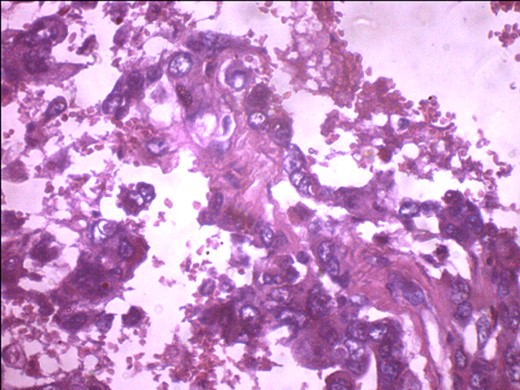

A 57-year-old woman presented with 5/12 history of left breast lump which gradually increase in size and became painful. Menarche was at 13 years without oral contraception. She had four confinements, the first being 20 years. Each child was breastfed for 8 months. No family history of breast cancer. Clinical examination showed breast asymmetry. Left breast was oedematous, shiny with extensive peau d'orange. Patient applied herbal preparations with multiple superficial skin excoriations. Outer quadrant breast mass was 8 cm, hard, with attachment to skin and underlying structures. No palpable axillary lymph node was felt and axillary ultrasonography, though desirable, was not done. Liver was not enlarged. Chest X-ray and abdominal ultrasound scan showed no involvement. Initial breast biopsy revealed an infiltrating atypical spindled tumour with hyperchromatic nuclei, which was both S100 and tyrosinase-positive. Tumour fungated with a darkly pigmented surface despite two cycles of neoadjuvant doxorubicin-based chemotherapy. Left simple mastectomy (Fig. 1) and axillary sampling (Fig. 2) of the sentinel and another slightly enlarged node were done, revealed a triple-negative invasive ductal carcinoma (Figs 3–6), with melanocytic differentiation (Figs 7 and 8), positivity for S-100 and patchy positivity for tyrosinase, an enzyme involved in melanin formation from dihydroxyl phenyl alanine. Only the sentinel node was involved, with the other showing reactive changes. Core biopsy of the tumour had ductal elements and was triple-negative.

PR-negative immunohistochemistry typing with rabbit progesterone antibodies.